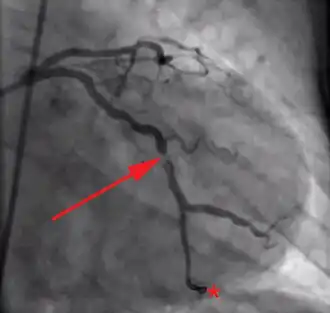

Acute coronary syndromes are classified to two major categories, according to the patient's electrocardiogram, and specifically the presence or absence of persistent (>20 min) ST segment elevation (or left bundle branch block).[2] Patients with acute coronary syndrome and ST elevation are said to have ST-elevation myocardial infarction (STEMI) and they tend to have one of their coronary arteries totally blocked.[3] Damage is reversible for approximately 20[4]-30[5] minutes after complete obstruction of blood flow; thereafter myocardial cell death ensues and progresses as time passes. Therefore, complete and sustained restoration of blood flow must be as prompt as possible to ensure maximum salvage of functional myocardium, a principle expressed in the maxim "time is muscle".[6] This is achieved with reperfusion therapy, which is based on invasive reopening of the affected coronary artery with primary percutaneous coronary intervention, or non-invasive breaking up of the responsible blood clot with a thrombolytic drug.[7]

Patients without ST segment elevation are said to have non-ST-elevation acute coronary syndrome and tend not to have full occlusion of a coronary artery. If there is evidence of myocardial cell death (especially elevated cardiac biomarkers) they are considered to have a non-ST-elevation myocardial infarction (NSTEMI); otherwise they are classified with unstable angina.[8] Their management is based on the estimation of their risk for adverse events. Patients at low risk can be adequately treated with medical therapy, in many ways similar to the one used for STEMI (but excluding thrombolytics). Those at moderate to high risk benefit from an early invasive strategy, which includes coronary angiography and, if necessary, revascularization with percutaneous coronary intervention or coronary artery bypass surgery.[9]

The concept of reperfusion has become so central to the modern treatment of acute myocardial infarction, that we are said to be in the reperfusion era.[53][54] Patients who present with suspected acute myocardial infarction and ST segment elevation (STEMI) or new bundle branch block on the 12 lead ECG are presumed to have an occlusive thrombosis in an epicardial coronary artery. They are therefore candidates for immediate reperfusion, either with thrombolytic therapy, percutaneous coronary intervention (PCI) or when these therapies are unsuccessful, bypass surgery.

Individuals without ST segment elevation are presumed to be experiencing either unstable angina (UA) or non-ST segment elevation myocardial infarction (NSTEMI). They receive many of the same initial therapies and are often stabilized with antiplatelet drugs and anticoagulated. If their condition remains (hemodynamically) stable, they can be offered either late coronary angiography with subsequent restoration of blood flow (revascularization), or non-invasive stress testing to determine if there is significant ischemia that would benefit from revascularization. If hemodynamic instability develops in individuals with NSTEMIs, they may undergo urgent coronary angiography and subsequent revascularization. The use of thrombolytic agents is contraindicated in this patient subset, however.[55]

The basis for this distinction in treatment regimens is that ST segment elevations on an ECG are typically due to complete occlusion of a coronary artery. On the other hand, in NSTEMIs there is typically a sudden narrowing of a coronary artery with preserved (but diminished) flow to the distal myocardium. Anticoagulation and antiplatelet agents are given to prevent the narrowed artery from occluding.